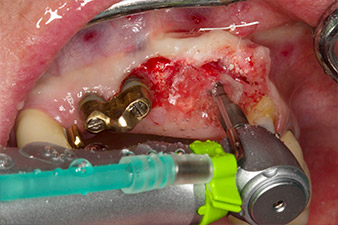

Nach primärer Abheilung werden die Weichgewebe mithilfe der basal unterfütterten Brücke ausgeformt. Zwei Monate später erfolgt die Freilegung mit einem leicht palatinal gelegten Kieferkammschnitt (Abb. 2).

Der Alveolarknochen erweist sich an Position 22 als ausreichend dimensioniert. Die Abbildungen 2 und 4 zeigen die Implantatbett-Aufbereitung, den Gewindeschnitt und die Implantation mit dem Implantmed.

Pilotbohrung mit dem neuen Implantmed und dem Winkelstück WS-56 L

Abb. 2: Zwei Monate später erfolgt die Pilotbohrung mit dem neuen Implantmed und dem Winkelstück WS-56 L (Programm P1, Übersetzung 1:1). Die Kühlung erfolgt über das links positionierte Sprayrohr (für Rechtshänder).